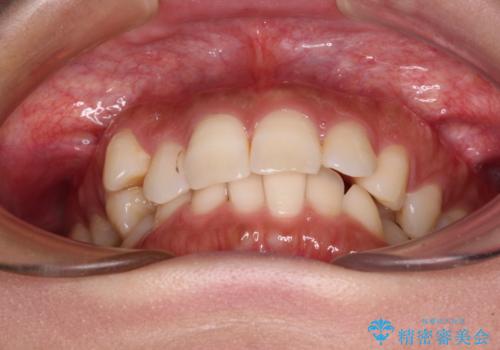

目立つ八重歯を改善 ワイヤー装置での抜歯矯正

- 目立つ八重歯を気にして来院された患者様です。

上顎小臼歯を抜歯するかどうか悩みましたが、八重歯の後方に失活歯があること、治療前に上顎正中が概ね人中に合っていることから、右上第二小臼歯を抜歯することとしました。

片側での抜歯であると、正中が抜歯した方向にずれていくため、左上の奥歯を遠心移動させる目的でアンカースクリューと補助装置を併用した上で、ワイヤー装置にて矯正治療を行うこととしました。